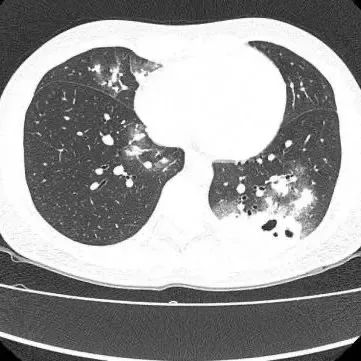

最新广州最新无症状感染:广州无症状感染者公布 近日广州30岁的夏女士(化名)因持续干咳一周到医院就诊胸部CT显示其双肺多发感染伴多发空洞形成被收入呼吸与危重医学科住院治疗医生查房时,捕捉到CT上形似“鬼脸”的特殊影像(即“鬼脸征”),并伴有“晕轮征”,高度怀疑隐... 龙腾环球视野2026-01-267 阅读0 评论